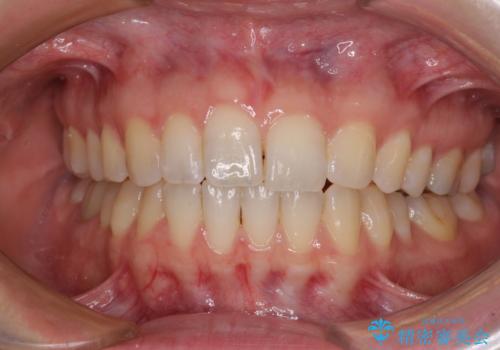

1日22時間の装着時間をしっかりと守ってくださったので、隙間がきれいに閉じ、口元の突出感も改善することができました。

- 上の前歯の隙間を気にして来院された患者様です。

インビザラインにより、上下の歯列を側方に拡大しつつ、前歯の隙間を閉じていくこととしました。